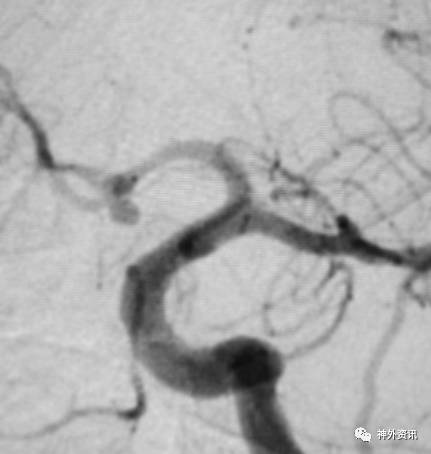

猪尾塑形

猪尾左行和右行

微导管尾端向下直立,头端向前弯曲时,头端相对左偏为左行,右偏为右行。

指向下方的颈内动脉眼段或床突段动脉瘤(颈动脉窝动脉瘤)

指向下方的颈内动脉后交通段或脉络膜段动脉瘤

(1)左侧颈内动脉-猪尾左行

(2)右侧颈内动脉-猪尾右行